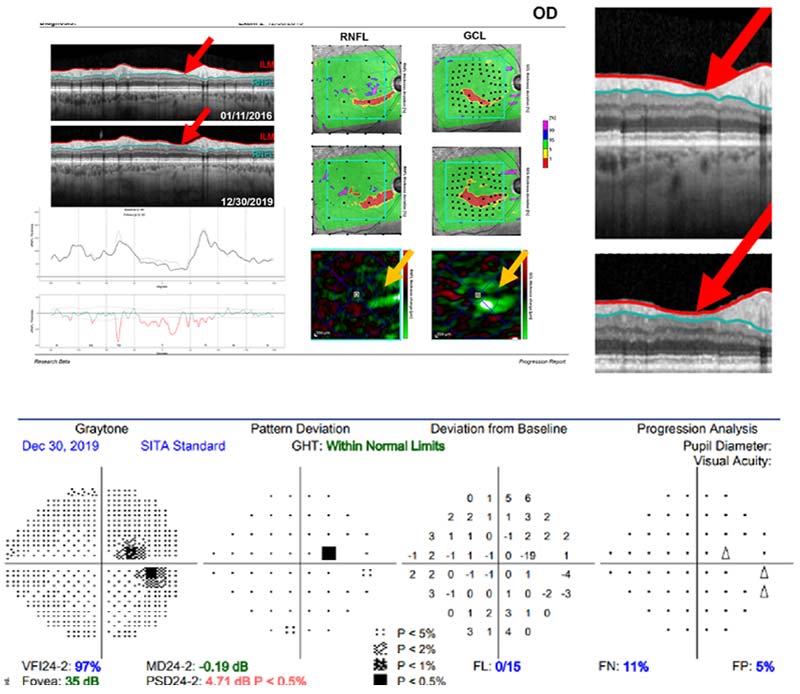

tomography of optic disc

Top panel: OCT of the optic disc with red arrows showing area of vulnerability.

Bottom panel: Visual field showing are of damage (black square) in the central part of vision.